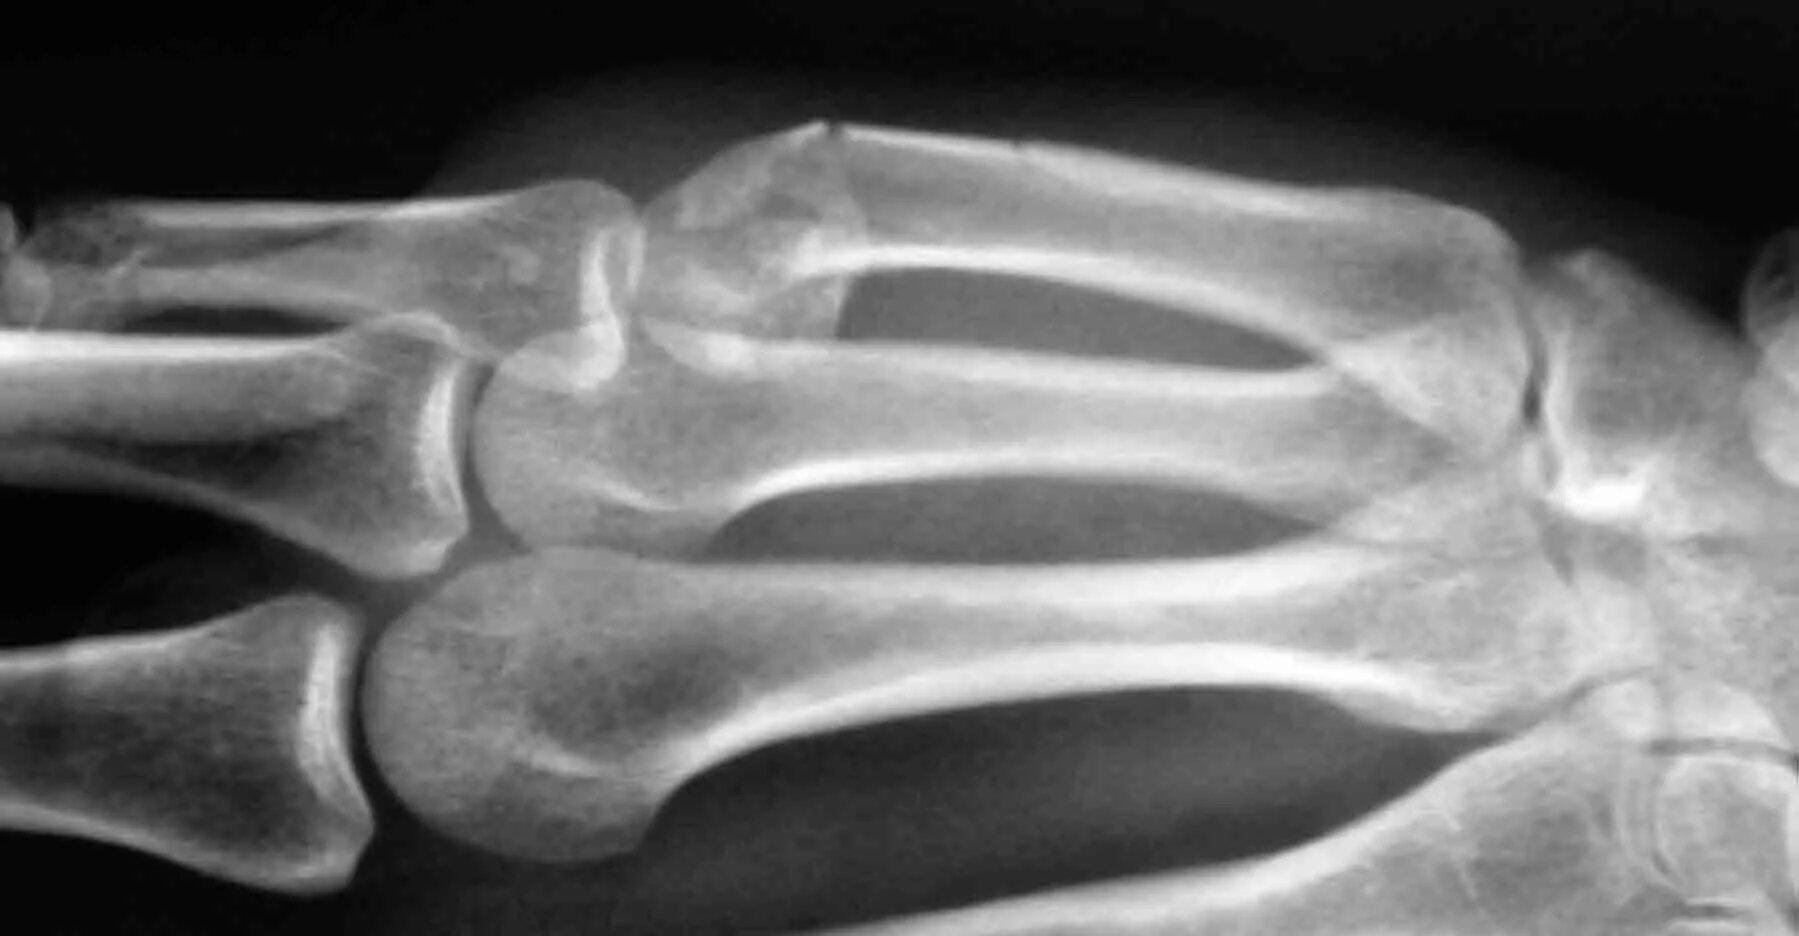

Перелом пятой пястной кости